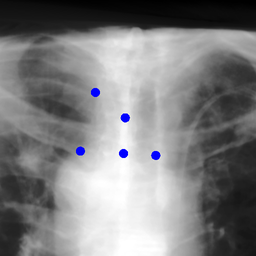

The dataset we use in the experiments is a cone-beam CT (CBCT) dataset captured for radiation therapy. The dataset contains 340 raw CBCT scans with each has 780 X-ray images. Each X-ray image comes with a geometry file that provides the registration ground truth as well as the information to reconstruct the CBCT volume. Each CBCT volume is reconstructed from the 780 X-ray images, and in total, we have 340 CBCT volumes (one for each CBCT scan). We use 300 scans for training and validation, and 40 scans for testing. The size of the CBCT volumes is 448×448×768448448768448\times 448\times 768 with 0.5 mm voxel spacing, and the size of the X-ray images is 512×512512512512\times 512 with 0.388 mm pixel spacing. During the experiments, the CBCT volumes are treated as the 3D pre-intervention data, and the corresponding X-ray images are treated as the 2D intra-intervention data. Sample X-ray images from our dataset are shown in Figure. Note that unlike many existing approaches [15, 17, 25] that evaluate their methods on small datasets (typically about 10 scans) which are captured under relatively ideal scenarios, we use a significantly larger dataset with complex clinical settings, e.g., diverse field-of-views, surgical instruments/implants, various image contrast and quality, etc.

Refer to caption

Figure 6: Sample raw X-ray images of our dataset.